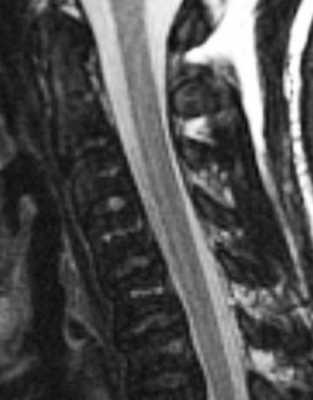

(Слева) На схеме сагиттального среза показана картина сливного гипертрофического эпидурального липоматоза дорзального отдела спинномозгового канала, вызывающего сдавление дурального мешка и минимальную компрессию спинного мозга. Последний оттеснен вентрально.

(Справа) Сагиттальный срез, Т2-ВИ грудного отдела позвоночника: эпидуральная клетчатка определяется в виде равномерного и гомогенного слоя, интенсивность сигнала которого соответствует интенсивности сигнала подкожной клетчатки. Также видны компрессионные переломы тел позвонков, связанные с остеопорозом, индуцированным приемом глюкокортикоидов.

(Слева) Сагиттальный срез, Т1-ВИ: гипертрофия эпидуральной клетчатки в дорзальном и вентральном отделе спинномозгового канала. Дуральный мешок уменьшен в передне-заднем направлении вследствие сдавления жировой тканью.

(Справа) На аксиальном Т1-ВИ определяются признаки выраженной гипертрофии эпидуральной клетчатки в поясничном отделе спинномозгового канала. Клетчатка в значительной степени сдавливает дуральный мешок, который принимает форму трилистника. Гипертрофированная клетчатка позволяет нам хорошо видеть связку Хоффмана, соединяющую заднюю продольную связку с вентральной поверхностью твердой мозговой оболочки.